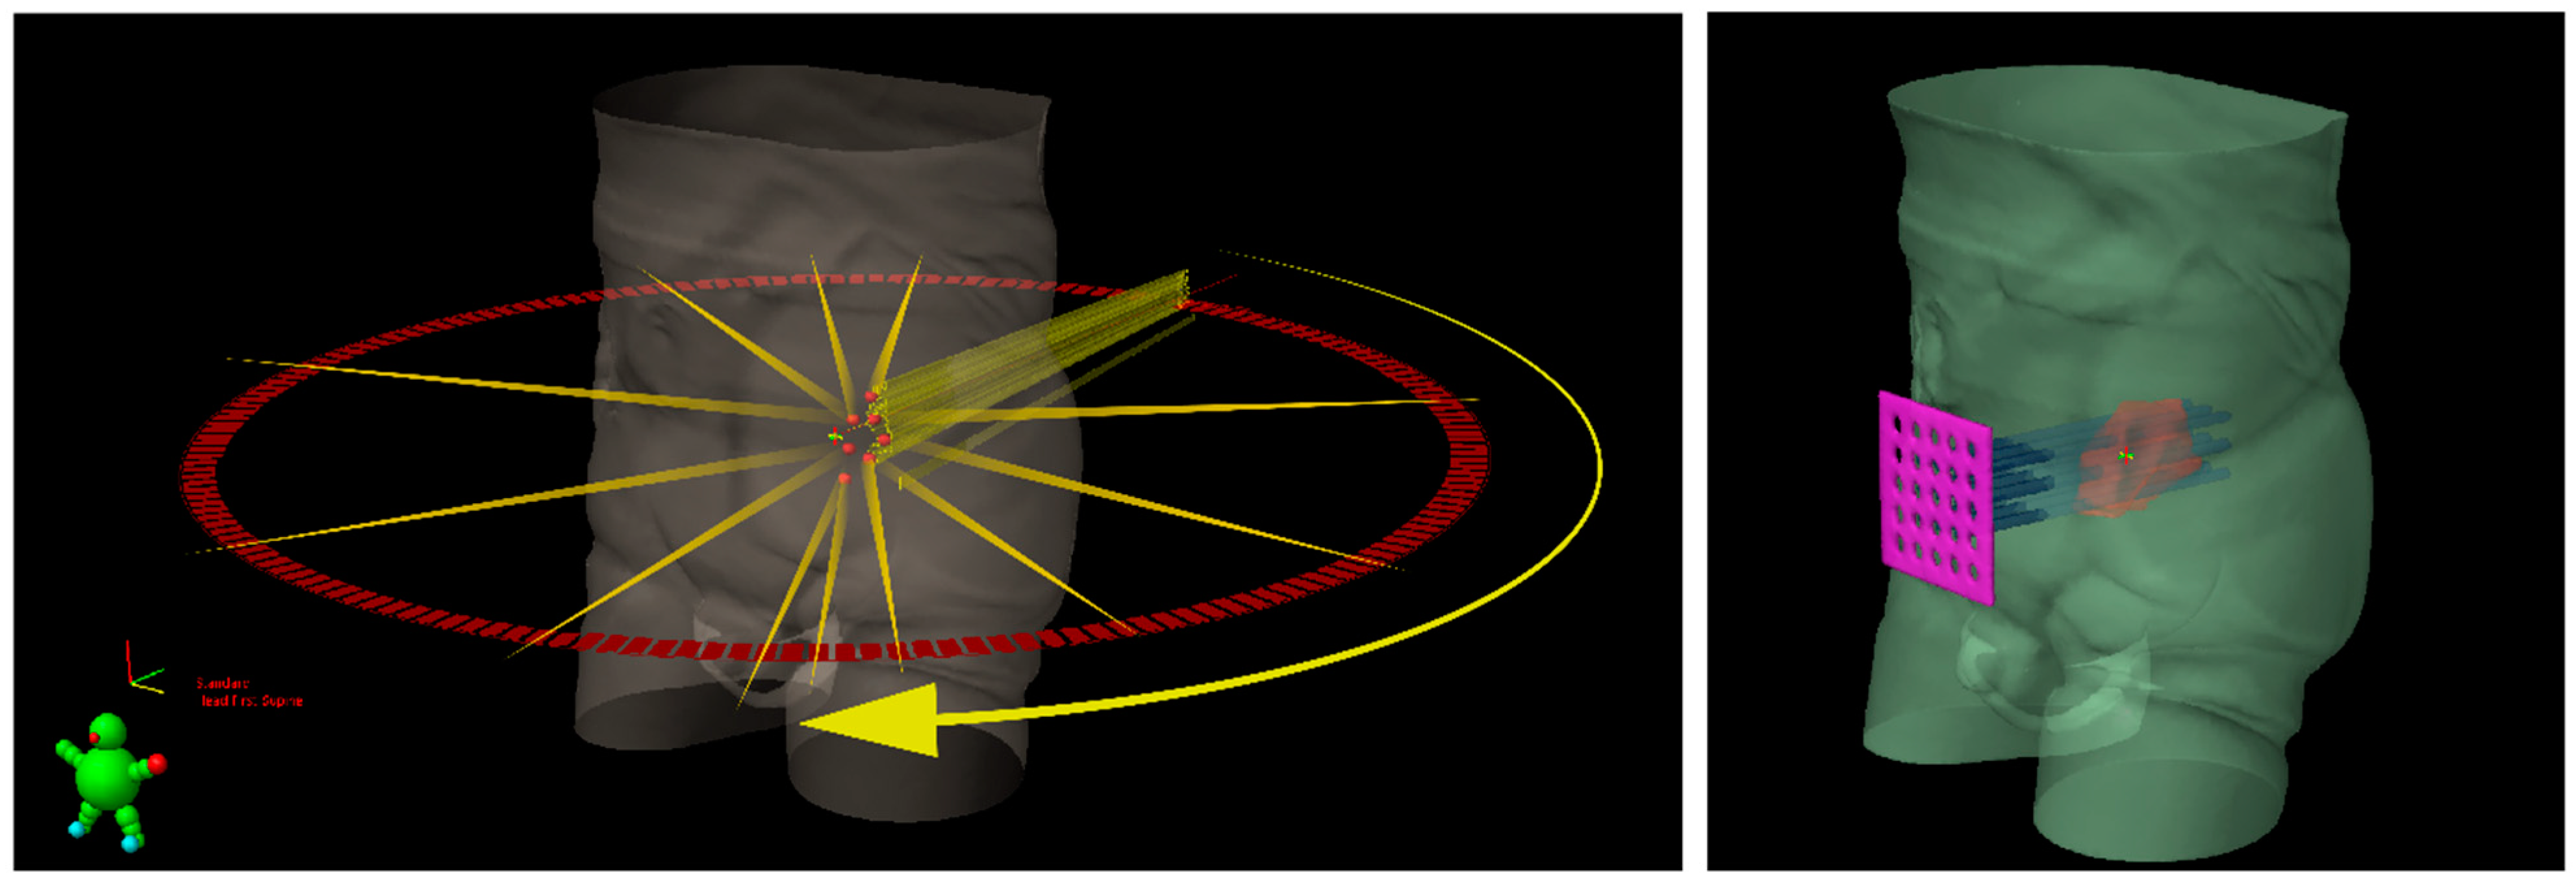

2. Lattice Radiotherapy: Concept

- Wu, X.; Perez, N.C.; Zheng, Y.; Li, X.; Jiang, L.; Amendola, B.E.; Xu, B.; Mayr, N.A.; Lu, J.J.; Hatoum, G.F.; et al. The Technical and Clinical Implementation of LATTICE Radiation Therapy (LRT). Radiat. Res. 2020, 194, 737–746. [Google Scholar] [CrossRef]

- E Amendola, B.; Perez, N.; Amendola, M.; Wu, X.; Ahmed, M.M.; Iglesias, A.J.; Estape, R.; Lambrou, N.; Bortoletto, P. LATTICE Radiotherapy with RapidArc for Treatment of Gynecological Tumors:Dosimetric and Early Clinical Evaluations. Cureus 2010, 2, 15. [Google Scholar] [CrossRef] [Green Version]

- Suarez, J.M.B.; E Amendola, B.; Perez, N.; Amendola, M.; Wu, X. The Use of Lattice Radiation Therapy (LRT) in the Treatment of Bulky Tumors: A Case Report of a Large Metastatic Mixed Mullerian Ovarian Tumor. Cureus 2015, 7. [Google Scholar] [CrossRef] [Green Version]

- Amendola, B.E.; Perez, N.C.; Mayr, N.A.; Wu, X.; Amendola, M. Spatially Fractionated Radiation Therapy Using Lattice Radiation in Far-advanced Bulky Cervical Cancer: A Clinical and Molecular Imaging and Outcome Study. Radiat. Res. 2020, 194, 724–736. [Google Scholar] [CrossRef]